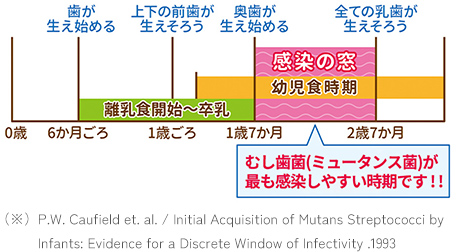

生まれたての赤ちゃんのお口には、むし歯の原生菌の1つであるミュータンスレンサ球菌が存在しないことをご存知でしょうか。むし歯菌は口から口へと感染すると考えられていますが、アメリカの疫学調査によるとミュータンスレンサ球菌の定着が1歳7ヶ月~2歳7ヶ月の期間に集中していることが明らかになっています。(※)お子様の予防はもちろん、この時期に育児に関わる大人が口腔管理を心がけることで、お子様のむし歯予防に一定の効果があると考えられます。

むし歯菌は口から口へと感染していくとご説明しましたが、原因菌の存在だけではむし歯になりません。歯の質やお口の中が汚れている時間、甘い物の摂取量など、様々な要素が組み合わさった時にむし歯ができるものです。だ液の量や歯質は先天的な要素に左右されますが、糖分の摂取量やお口の中の汚れは環境を変えれば改善が期待できます。お子様が小さい頃は糖分が多いおやつを控え、歯磨きの習慣を作ってあげましょう。